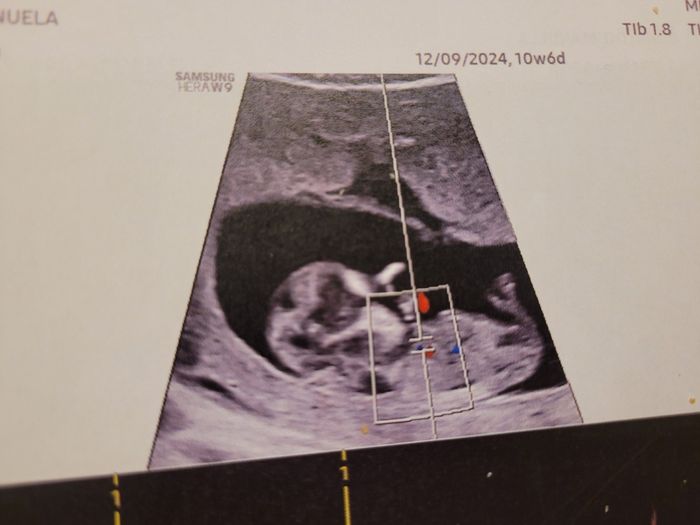

Ciao ragazze, lunedì scorso ho fatto eco genetica a 11+5 ma bebè misurava 12 settimane, ho fatto dna fetale che dovrebbe arrivare questa settimana, ma nel frattempo per ingannare il tempo e l’ansia, c’è qualcuna che se ne intende di nub theory? Io un...